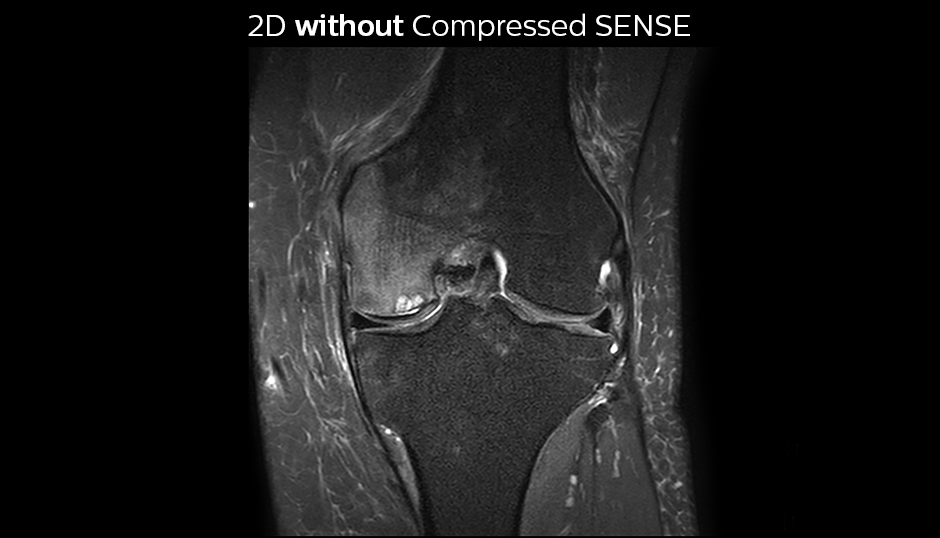

A good acquisition time with high resolution is obtained when moving from three 2D acquisitions in three planes to one 3D acquisition with Compressed SENSE. In this example, Compressed SENSE with 3D VIEW PD SPAIR is 50% faster than three separate 2D scans and has improved spatial resolution.

Without Compressed SENSE Scan time 2:55 + 3:37 + 3:51 = 10:23 min. Voxel size 0.55 x 0.65 x 3 mm

Three separate 2D PD scans in three orientations

With Compressed SENSE factor 10 Scan time 5:03 min. Voxel size 0.6 x 0.6 x 0.6 mm

3D VIEW PD SPAIR high resolution knee